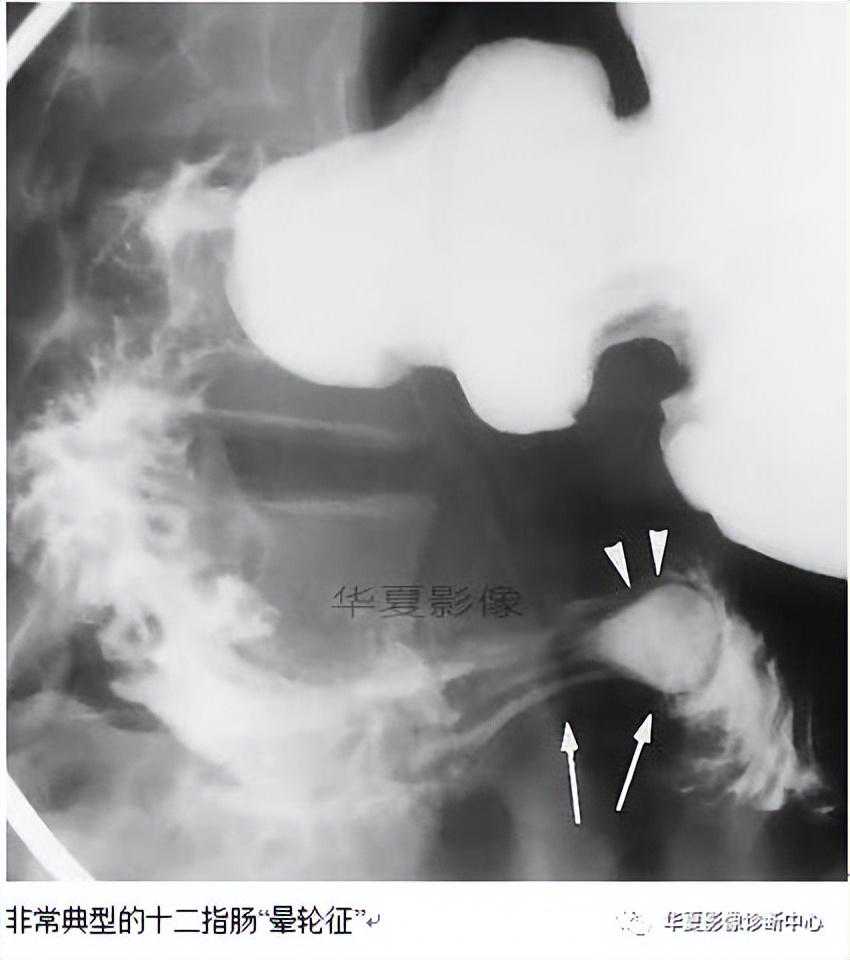

【影像表现】十二指肠肠风向袋征见于日服钡剂上消化道造影。该征象包含一个充满钡剂的囊袋及其周围一圈边界光整的窄的透光线,充钡的囊袋完全位于十二指肠内,钡剂越过该囊袋到达十二指肠远端。

【征象解释】十二指肠风向袋征被认为是十二指肠腔内憩室的典型表现。窄的透光圈代表腔内猫膜形成的隔或蹼,它是由于胚胎期第7周时前肠腔上皮细胞吸收后正常十二指肠再通时发生异构而不完全再通所形成的口随着时间的推移,在肠管持续不断的蠕动下,该隔膜被动地逐渐延长,形成腔内憩室,并形成风向袋状结构。由于在上消化道造影时形成憩室周围的薄透光带,因此也有人称其为晕轮征。

【讨论】十二指肠腔内憩室是少见的发育异常,通常见于十二指肠降部。绝大多数起源于靠近肝胰壶腹附近并且与肠蠕动方向一致。少数情况下起源于十二指肠水平部或向肠蠕动相反方向延伸。憩室与肠壁的附着处通常小于肠壁周径的1/2,只有少数报道憩室附着于肠壁全周,此时位于隔膜中央或周边的缝隙或小孔能允许肠内容物通过。与胃肠道其他部位的憩室不同,十二指肠腔内憩室的两面均为乱膜层,上皮细胞层上只有很薄的纤维肌层组织,血管结构很少。

十二指肠腔内憩室的诊断主要依据上消化道造影。其主要表现类似一个风向袋吹向十二指肠。该影像表现是具有特异性的,没有其他的病变有此表现,不必进行鉴别。然而,当憩室被液体或其他物质充填时,或当造影时憩室内没有被钡剂充盈时,其表现可能类似于带蒂息肉、乳膜下肿瘤或胆总管囊肿。内镜检查也是有特异性的,表现为正常十二指肠乳膜上出现一个自袋口文献报道有个别病例是通过CT、超声内镜、静脉胆道造影、PTC或ERCP等检查发现的。

总之,掌握十二指肠风向袋征这一特征性的十二指肠腔内憩室的表现,对于正确诊断这一少见疾病是非常重要的。